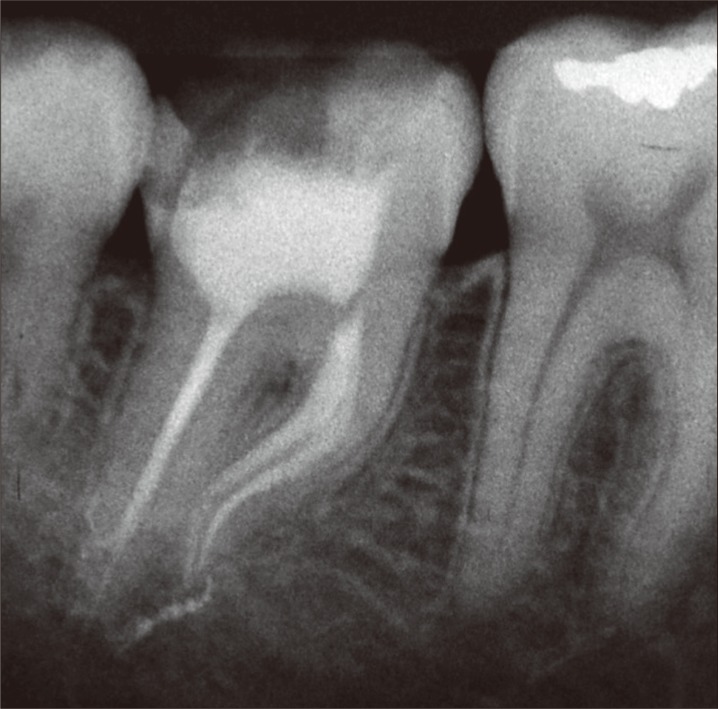

The patient, a 22-year old man, complaining of moderate pain in tooth #47 upon chewing, was referred to the Dental Clinic of the Federal University of Amazonas, Brazil. The patient did not have any systemic diseases and were not under any type of medication or drugs. Intraoral examination revealed the presence of a temporary restoration. The tooth was tested for pulp sensibility with Endo Frost spray (Roeko GmbH & Co., Langenau, Germany) and responded positively to the cold test, and negatively to the mobility test. The periapical radiographic examination revealed that the temporary restoration was extremely deep, since the tooth had already been submitted to pulpotomy procedure. Moreover, an accentuated dilaceration in the mesial root, a developmental anomaly characterized by an abrupt change in the axial inclination of the root, was observed. Also, no periapical lesions were observed (Figure 1).

The tooth was diagnosed as asymptomatic irreversible pulpitis and endodontic treatment was instituted. After local anesthesia (Xylestesin 2%, Cristália Produtos Químicos Farmacêuticos Ltda., Itapira, SP, Brazil) and rubber dam isolation (Hygienic, Coltene/Whaledent AG, Alstatten, Switzerland) of the operative area, the temporary restoration was removed and pulp chamber access procedure using spherical burs No. 1013 (KG Sorensen, São Paulo, SP, Brazil) and tapered flame shaped burs No. 2200 (KG Sorensen) was performed. Next, the root canals orifices were located with the aid of a straight exploratory probe. The glide path was performed using #10 K-files (Dentsply Maillefer, Ballaigues, Switzerland) and Pathfile #13, #16 and #19 (Dentsply Maillefer) up the working length of 18 mm.